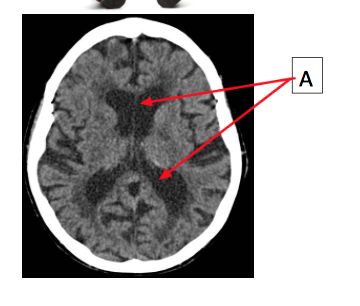

This is Arnolds head CT

What is structure A?

Why is it black?

Lateral ventricles

CSF is black as liquid and is within the cerebral cortex